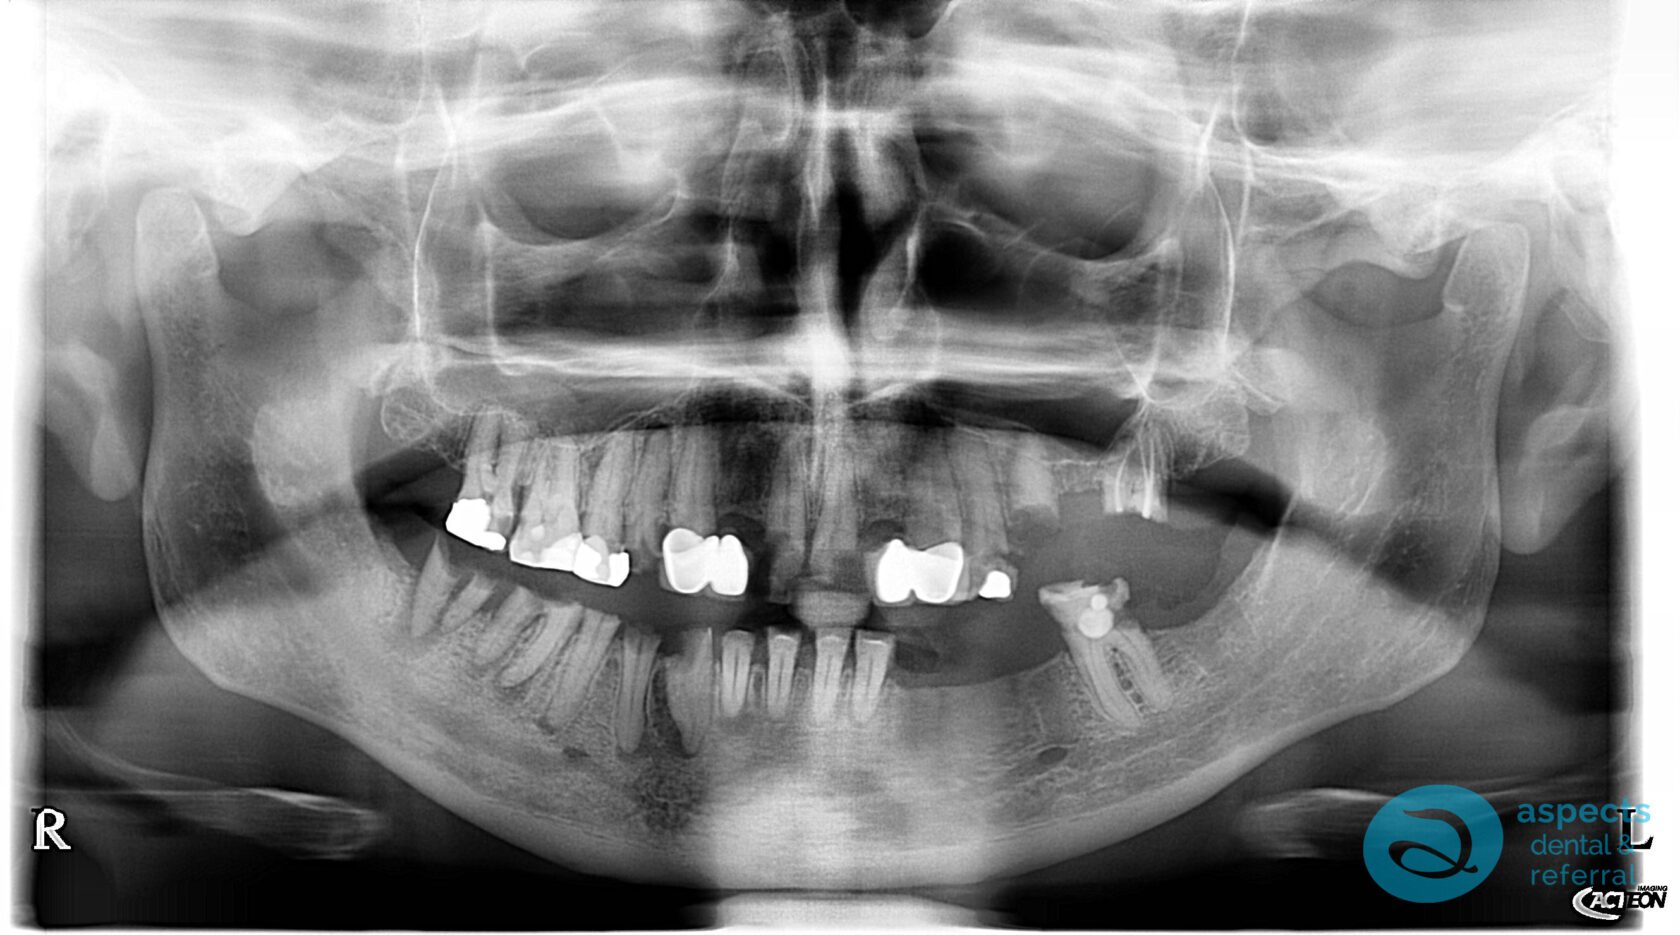

Our Dental Patient initially presented with neglected dentition, with the majority of teeth deemed non-restorable due to extensive decay and/or Periodontal Disease. Comprehensive treatment planning was carried out, and it was determined that full-mouth extractions were necessary.

Before Implant-Retained Overdentures Xray